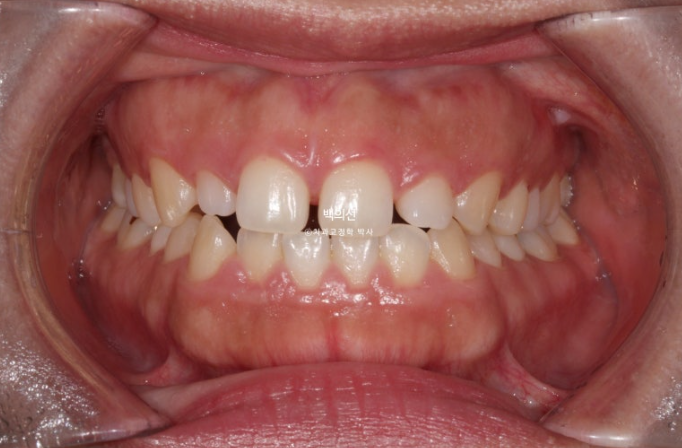

2년 전 교정치료를 위해 오신 환자분입니다.

고치고 싶은 것은 세가지 입니다.

벌어짐

비대칭

무턱

아래턱이 좌측으로 틀어져 있는 골격적 비대칭이 있고 앞니 중심선도 어긋나 있습니다.

위 앞니가 아래 앞니를 덮지 못하는 개방교합이 보입니다.